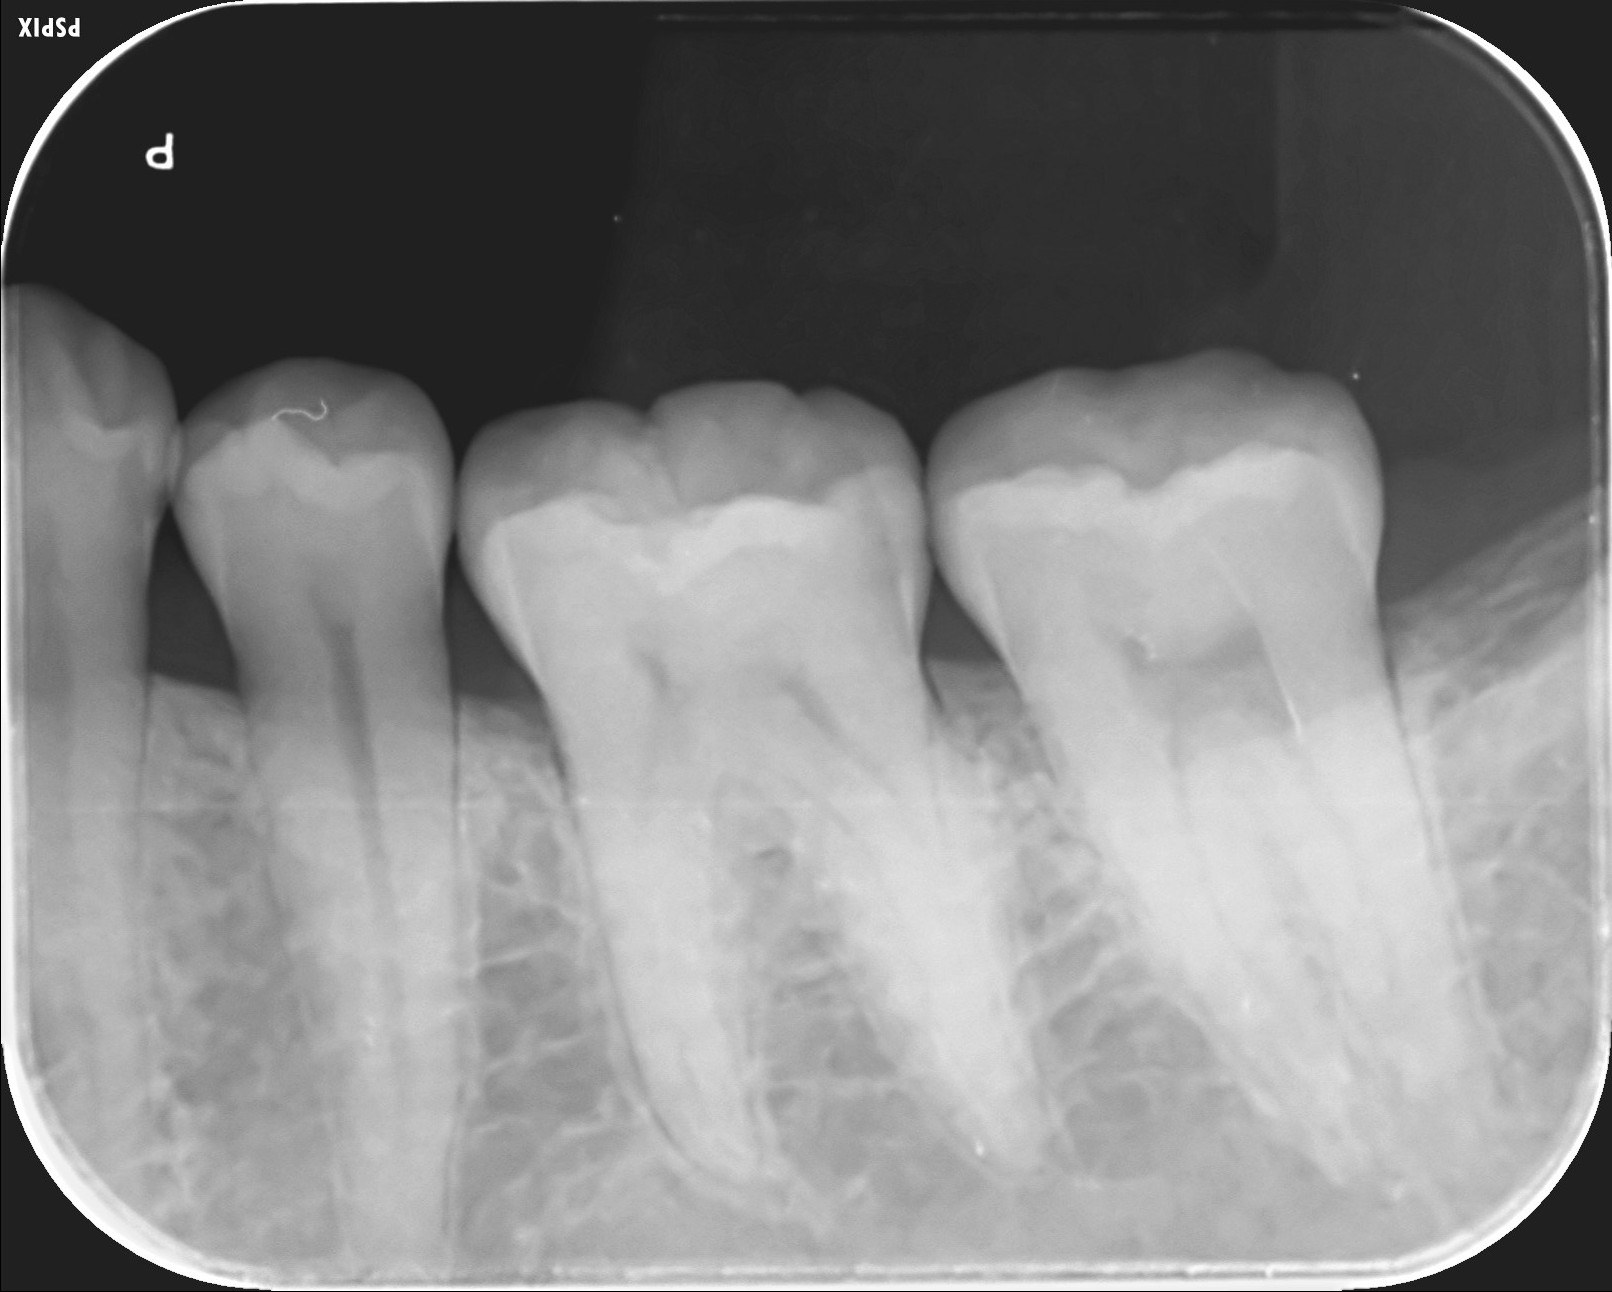

X線写真

6番の遠心隣接面が黒くなっています。 虫歯があります。痛みはなかったようです。 -